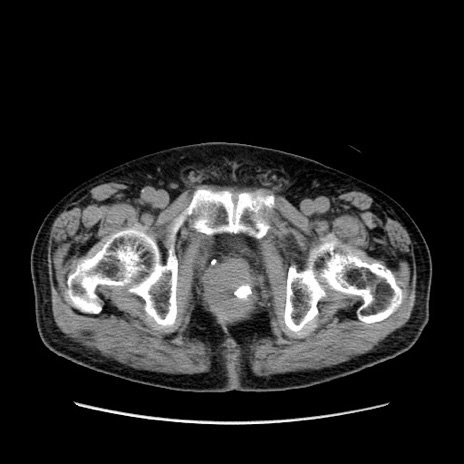

症例24(横断像)

【症例】80歳代男性

【主訴】左側腹部痛、嘔吐

【現病歴】本日早朝より左腹部に痛みあり。昼頃嘔吐認めたため、救急要請。

【既往歴】直腸癌(Mile手術)、胆摘

【身体所見】意識清明、BT 35.9℃、BP 221/93mmHg、SpO2 97%(RA) 、腹部:左ストーマ周囲に限局性の腹部膨隆あり。 膨隆部自発痛・圧痛あり・軟。

【データ】WBC 7700、CRP 0.09